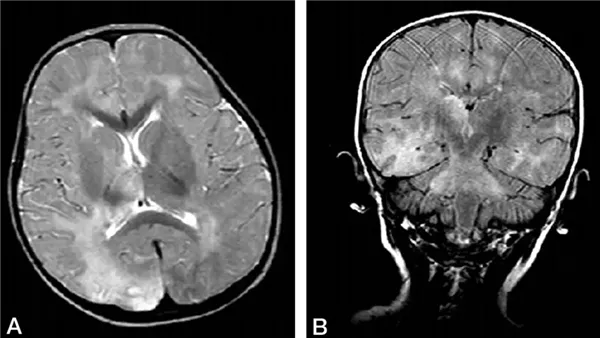

مرض عصبي نادر يحدث نتيجة بقاء فيروس الحصبة في الجسم مع حدوث طفرات لاحقة، وتظهر أعراضه عادةً بعد 6 – 10 سنوات من الإصابة الأصلية.

والأعراض تبدأ بتغيرات في السلوك والذاكرة، ثم تتطور إلى تشنجات، حركات لا إرادية، تلف شديد في الدماغ، ثم الوفاة.